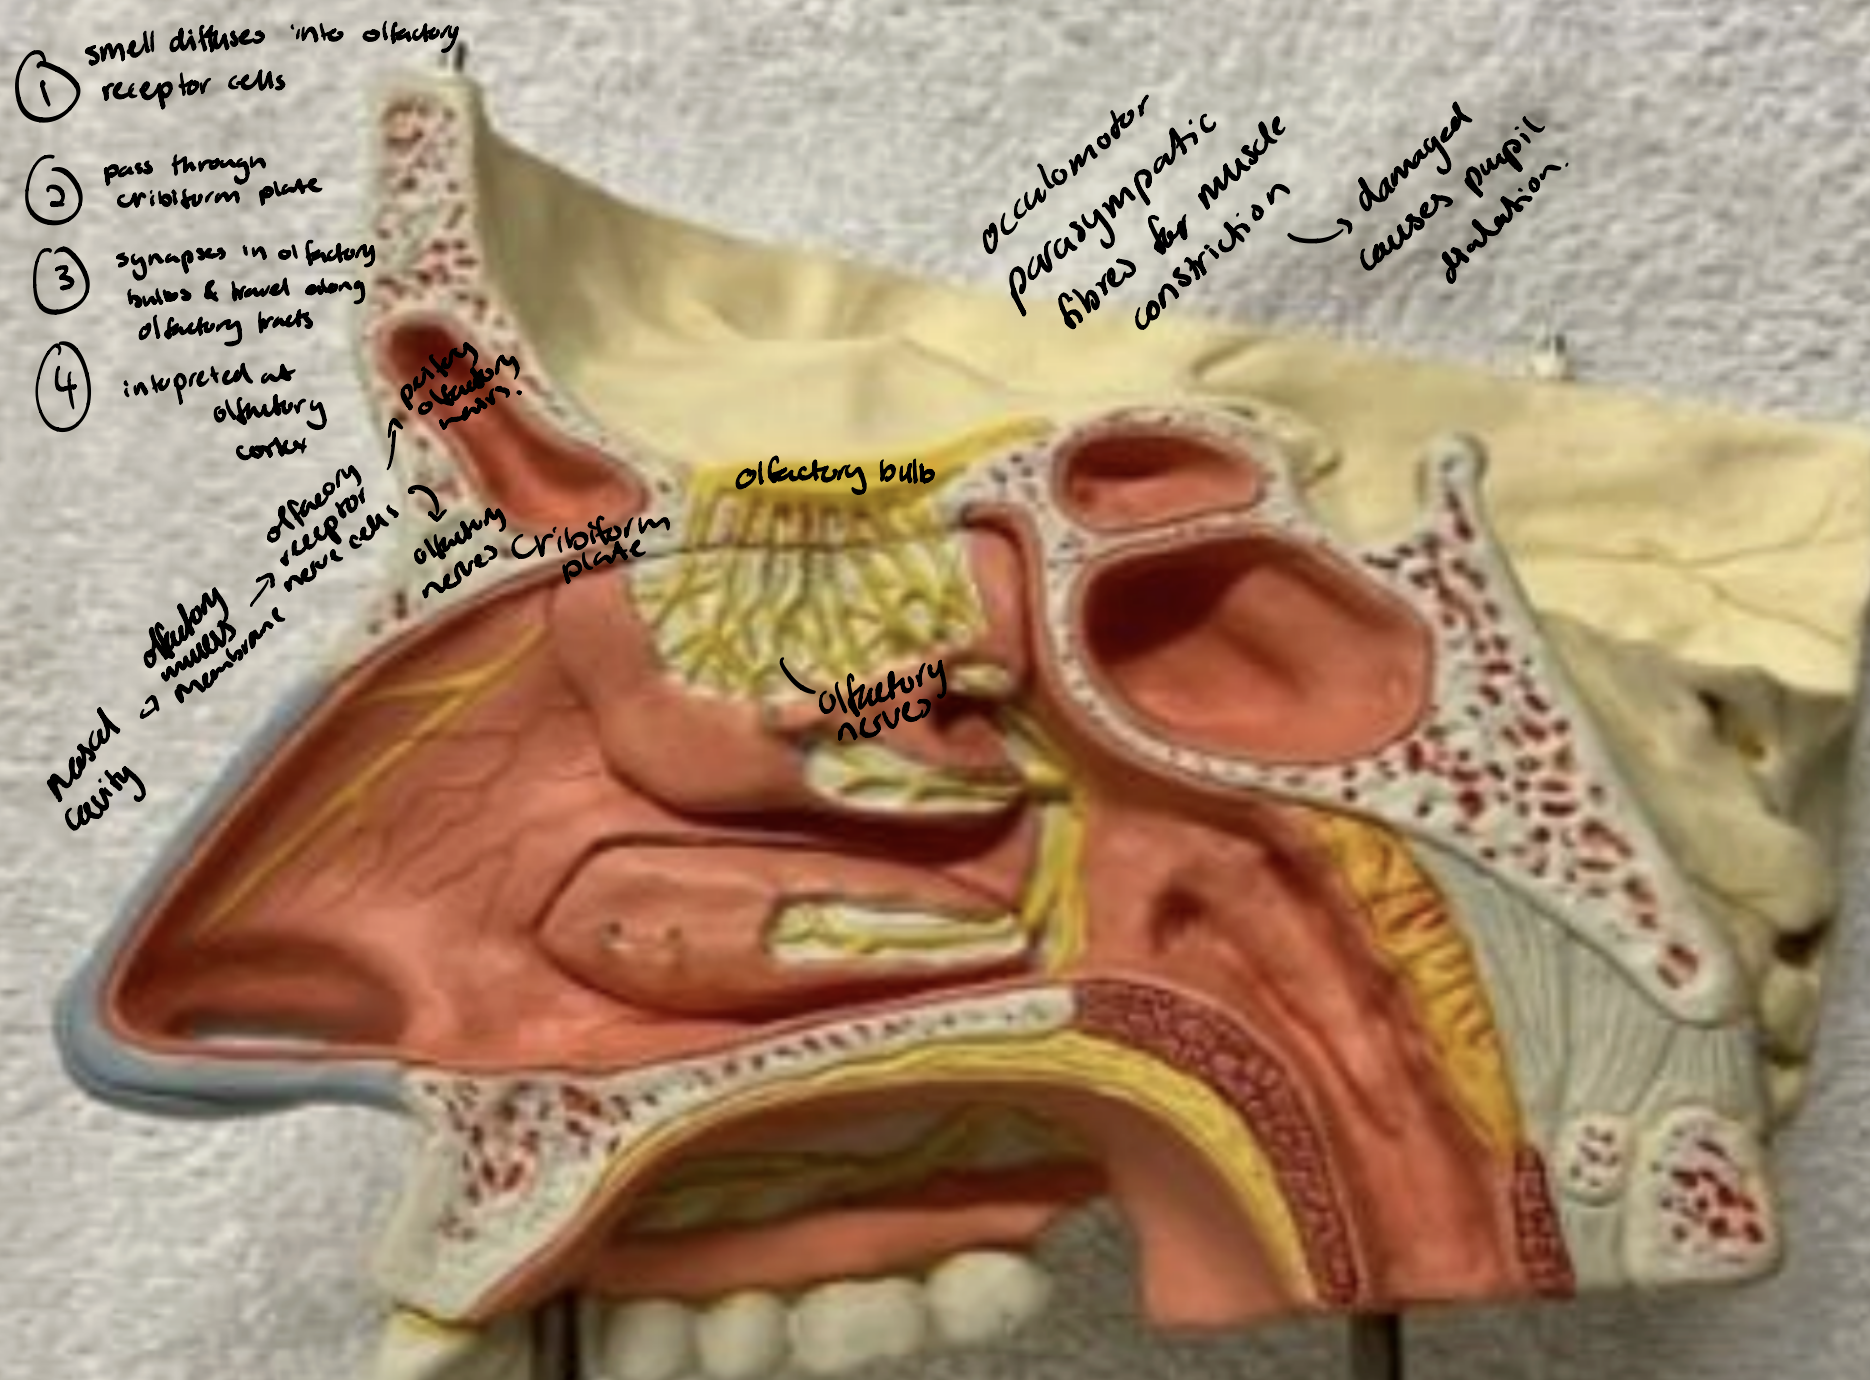

Pathway of CNI